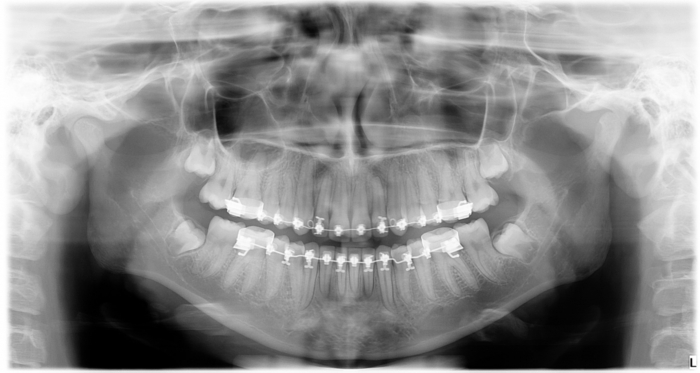

Rx Panorâmica - 2018, com os caninos em posição